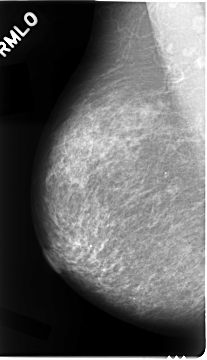

Digital Database for Screening Mammography

Volume: cancer_02 Case: C-0023-1

RIGHT_CC LINES 4664 PIXELS_PER_LINE 2744 BITS_PER_PIXEL 12 RESOLUTION 50 NON_OVERLAY

RIGHT_MLO LINES 4680 PIXELS_PER_LINE 2680 BITS_PER_PIXEL 12 RESOLUTION 50 NON_OVERLAY